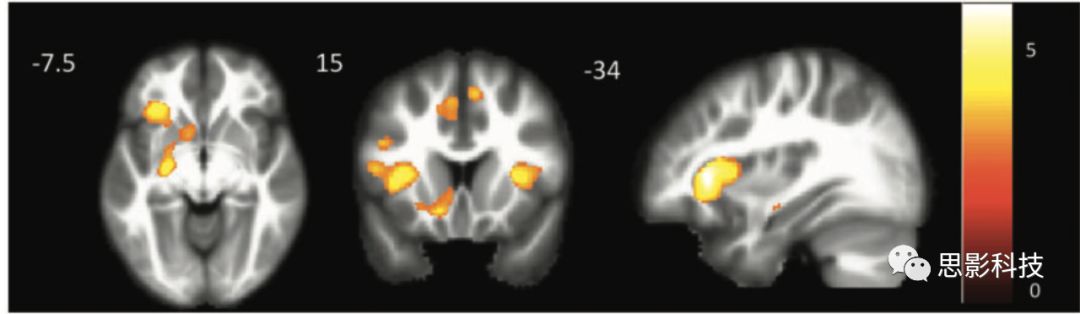

4描述了作者在之前的健康對照研究中確定的基于額下回種子點的靜息狀態(tài)功能網(wǎng)絡(圖中用紅色、藍色和綠色標出的區(qū)域都屬于該網(wǎng)絡)。在該網(wǎng)絡中,nfvPPA被試中顯著萎縮的區(qū)域包括:雙側(cè)輔助運動區(qū)、左側(cè)額下回、左側(cè)中央前回和中央后回、左側(cè)殼核、右側(cè)額下回和中央前回。

對處于這個網(wǎng)絡的11個種子點的分析發(fā)現(xiàn),僅在左側(cè)顳中下回的感興趣區(qū)域顯示出平均灰質(zhì)體積和治療效應顯著的偏相關(guān)(控制失語癥的嚴重程度)(r = 0.875, P = 0.002)。

額下回靜息網(wǎng)絡和治療效應與顳中下回灰質(zhì)體積顯著偏相關(guān)